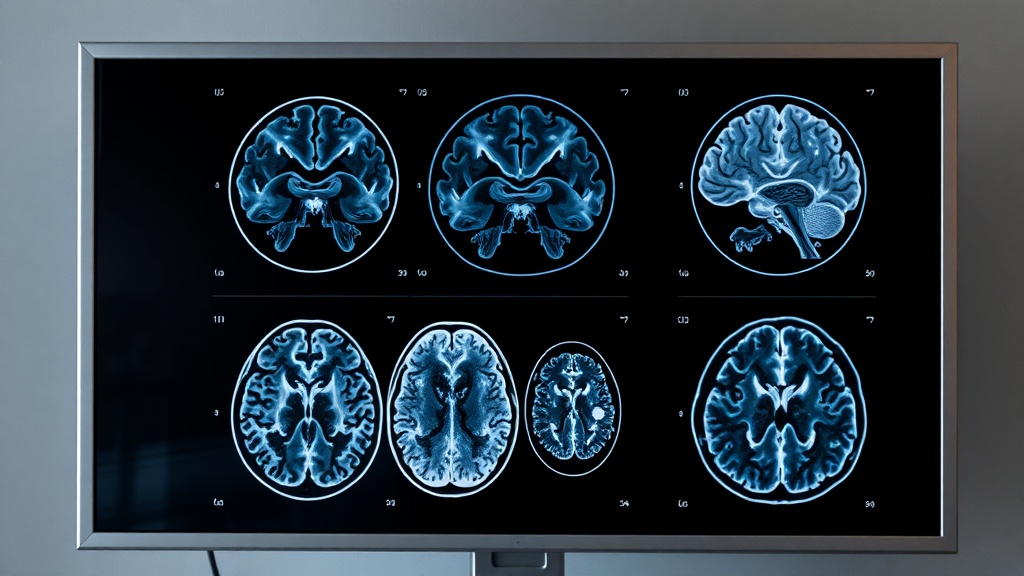

Researchers have identified two new modifiable risk factors for dementia: high cholesterol after age 40 and untreated vision loss. These findings, published in The Lancet, add to 12 previously recognized factors, collectively accounting for nearly 49% of global dementia cases. This highlights the critical role of managing cardiovascular health and sensory well-being.